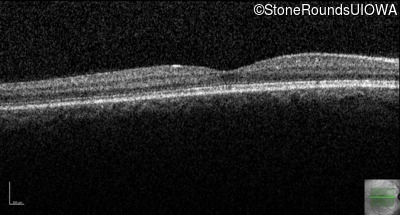

Congenital Stationary Synaptic Dysfunction (IA2g)

Congenital Stationary Synaptic Dysfunction (IA2g)

| Congenital Stationary Synaptic Dysfunction | CABP4 | Arg49Stop CGA>TGA | IVS1+1 G>T | AR |